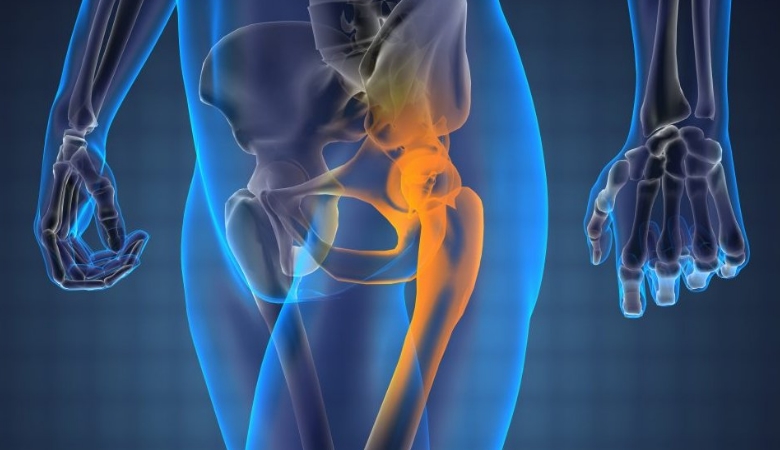

Данное новообразование поражает длинные и плоские трубчатые кости, к примеру, ребра (в 10% случаев), больше- и малоберцовую кости (20%), бедренную кость (20%), кости таза (20%), а также позвоночник, ключицу, лопатку.

На фото: Саркома Юинга правой подвздошной кости. Тазовая рентгенограмма 5-летней девочки показывает большое литическое поражение.

- нижние конечности и таз (например, саркома Юинга подвздошной кости) – хромота;

Терминальный период заболевания, сопровождающийся множественными метастазами, имеет неблагоприятный прогноз. Например, саркома Юинга подвздошной кости 4 стадии связана с очень высокой вероятностью летального исхода – около 90%. Но при условии использования высоких доз химио- и лучевой терапии, а также в случае проведения трансплантации костного мозга, выживаемость повышается до 30%.

- Образование в подвздошной кости – таз человека включает большую кость, которая нередко подвергается атаке атипичных клеток. Для диагностики используют биопсию, на рентгене определить болезнь затруднительно.